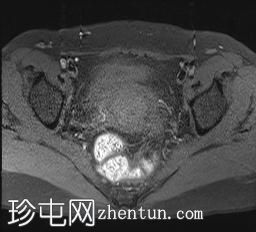

轴位T1加权像

脂肪抑制像

可见局部晚期浸润性内生型宫颈癌,肿瘤大小为30 x 32 x 48 mm。该肿瘤已侵犯宫颈前唇和后唇的深层间质,以及子宫肌层的下段。

此外,肿瘤还累及宫旁组织。影像学检查发现异常淋巴结肿大,最大短轴直径(SAD)为10 mm,位于髂总血管分叉处和髂内动脉链下方。该淋巴结肿大在弥散加权成像(DWI)上显示水限制,且增强扫描后可见强化。

宫内节育器(IUD)位于子宫内正常位置。左侧子宫底壁内肌瘤大小为15 x 16 mm(FIGO 4期)。子宫内膜厚度约为3 mm,未见宫腔内病变。双侧卵巢外观正常,未见实性或囊性病变。